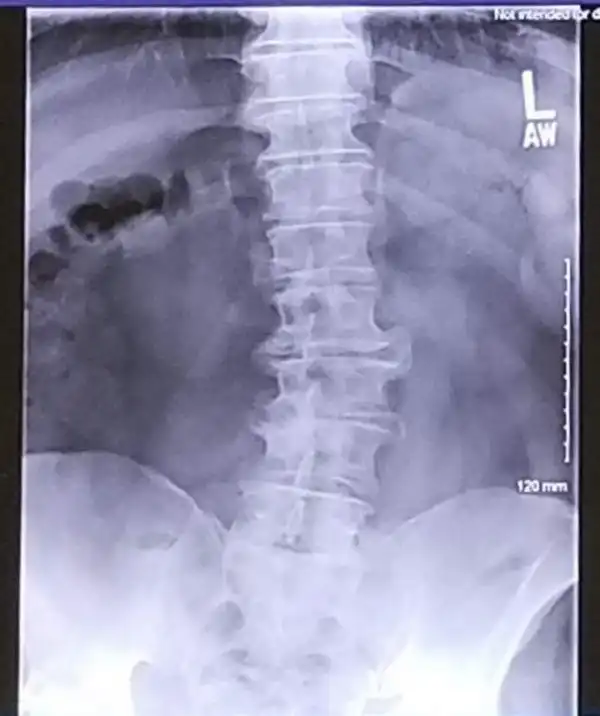

"Скинул рентген жене, надеясь на сочувствие. Она сказала, что мой позвоночник похож на проселочную дорогу"